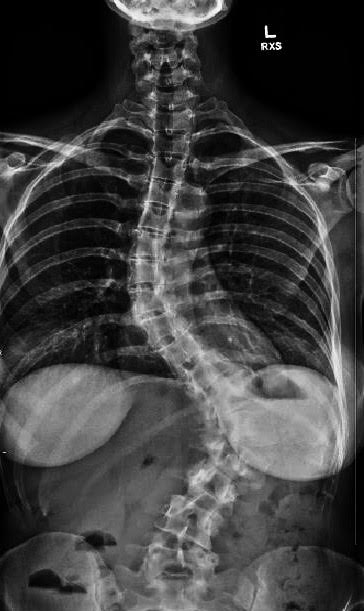

So today instead of posting about my love for Lululemon Striped Wunder Unders, I am posting some x-ray pictures, that I am sure you have all been dying to see. I waited impatiently for this CD to show up in the mail so I could finally post them and although it wasn’t a new pair of J brand jeans or an amazing spring blouse, I was still super excited to finally get it in the mailbox. Weird, right? Of course, once I actually look at them, its depressing and horrible. Not only does my spine curve side to side in an S, but it also curves front to back which is what causes my hump and is called Kyphosis. What you can’t see in these pictures is how my spine twists and rotates as well. And if you look really close, you can see my ribs basically rests on my hip bone. Sounds cool, huh?